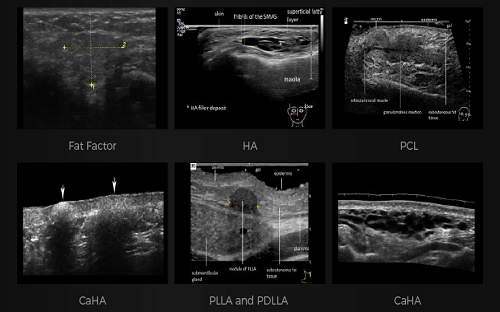

PAU2C aesthetic skin ultrasound device is portable and easy to use for aesthetic medicine. Handheld design allows aesthetic physicians to perform ultrasound whenever patients are in need. Aesthetic medicine ultrasound device works for medical beauty, clinic, hospitals, beauty salon. Our medical beauty ultrasound device that connects with WIFI without restrictions of wiring. Support windows, android, and IOS. Supported ultrasound exam presets for cosmetic medical services include fat factor, HA, PCL, CaHA, PLLA and PDLLA.

PAU2C is a game-changing ultrasound device for aesthetic and medical professionals, combining intuitive usability with advanced features to meet modern clinical and beauty workflow demands. Whether used to evaluate fat distribution, track filler efficacy, or assess tissue response, PAU2C delivers the precision, speed, and dependability professionals need for exceptional patient outcomes.